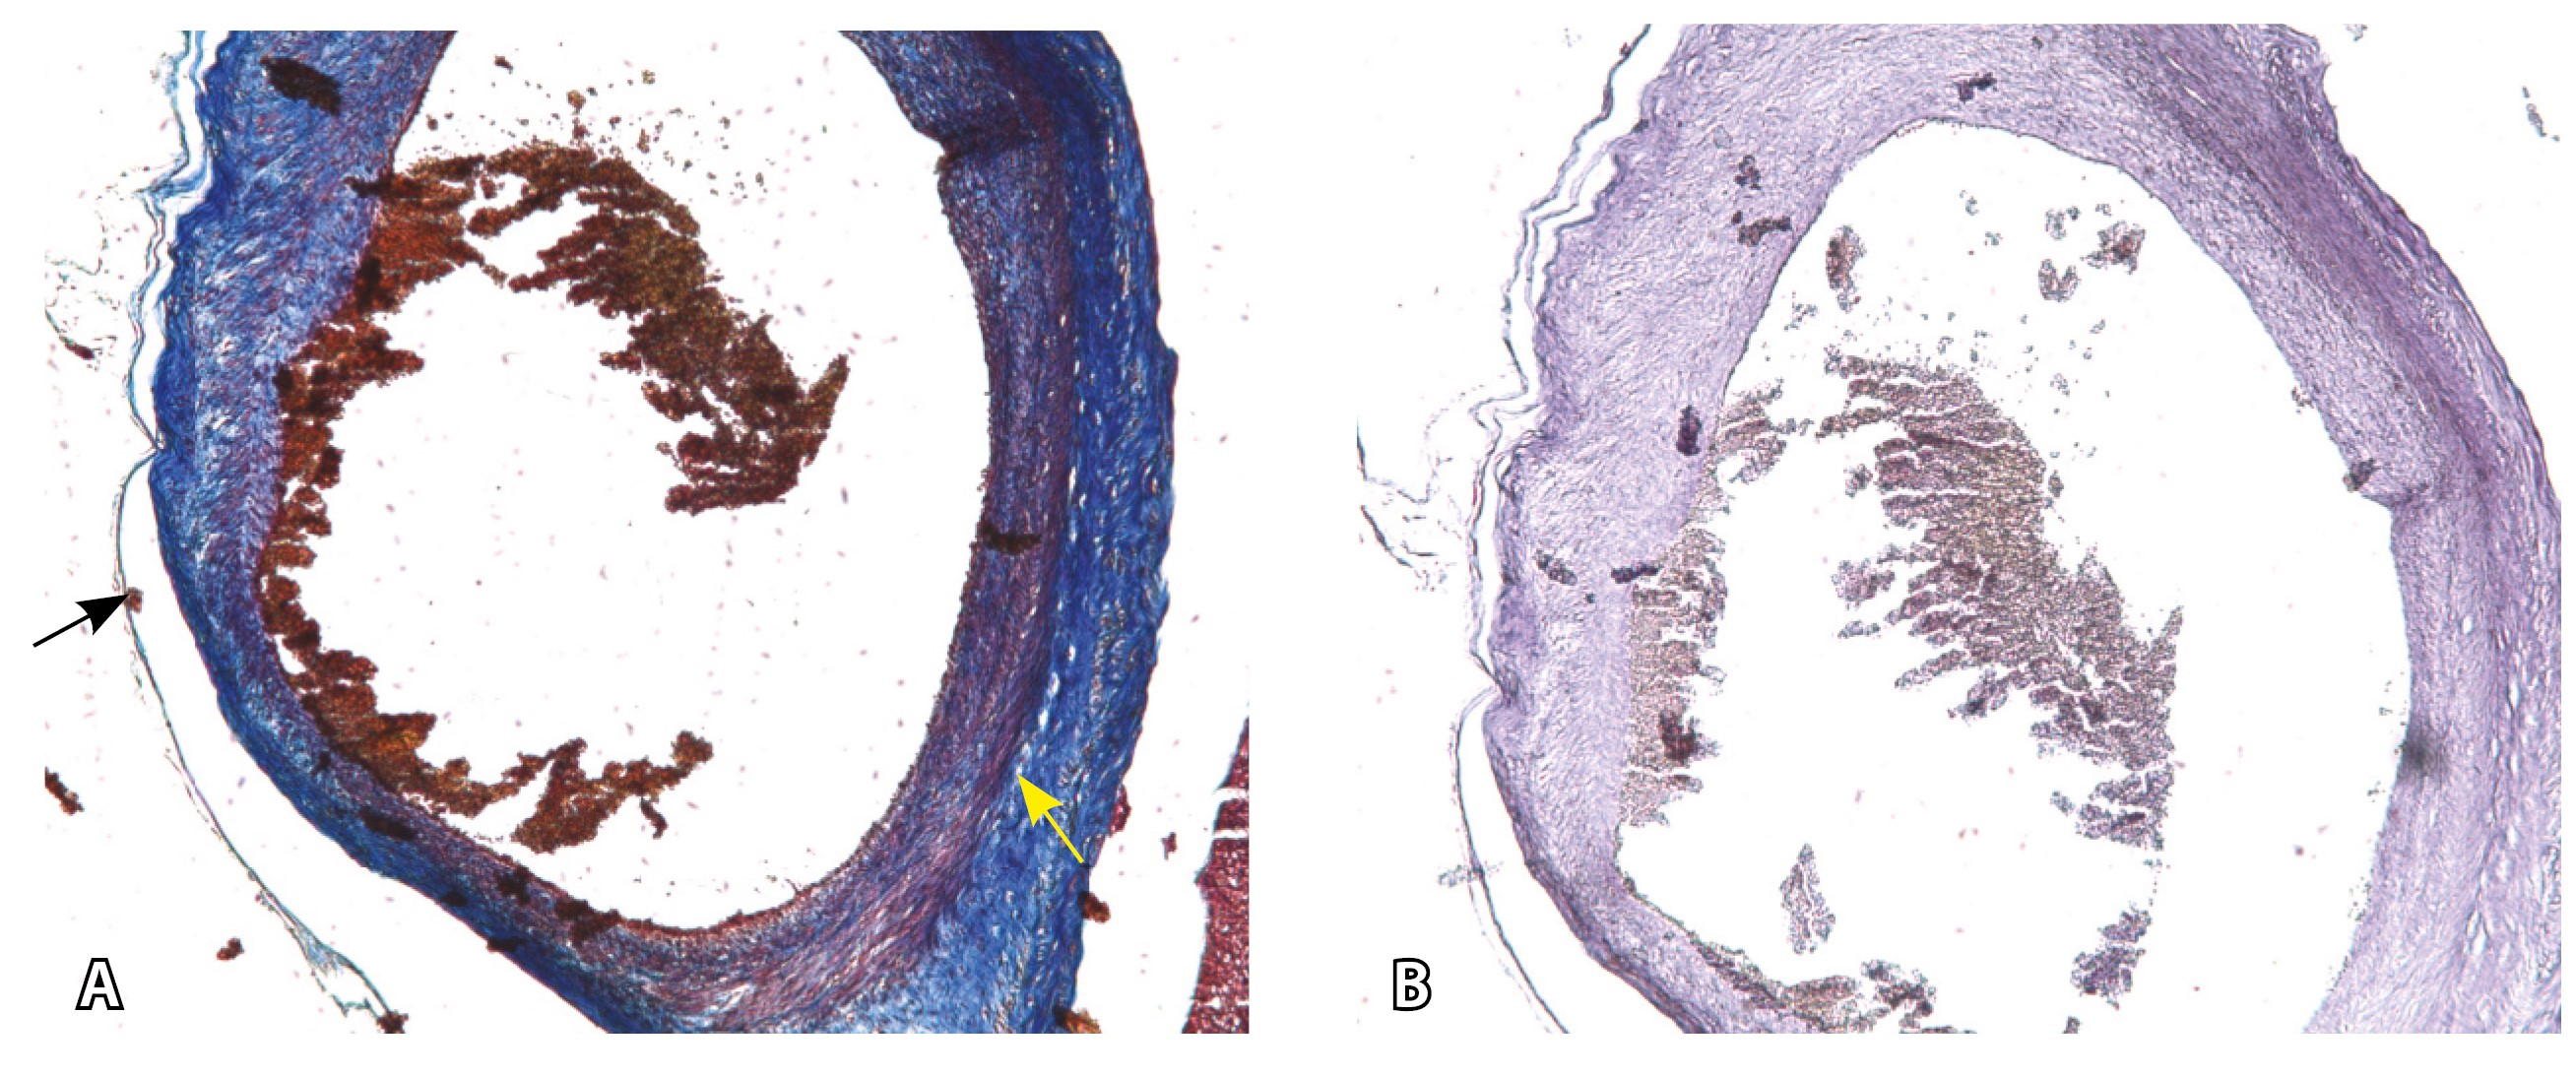

Рис. 13. Самые крупные сосуды в пределах серозной оболочки стенки матки: А, Б – серийные срезы артерии; × 50. При окраске по Маллори (А) видна тонкая полоска мезотелия (черная стрелка), слабо дифференцированная мышечная стенка артерии, вокруг нее – плотная коллагеновая оболочка (желтая стрелка), в просвете определяются тромботические массы. При окраске по Вейгерту (Б) наблюдается полная потеря внутренней и внешней эластических мембран

Главным отличием крупных сосудов в составе серозной оболочки является то, что морфологически они находятся в пределах стенки матки. Об этом свидетельствует наличие в операционном материале тонкого поверхностного слоя мезотелия, отделяющего матку от брюшной полости (рис. 11). Его невозможно визуализировать методом МРТ из-за особенностей метода и толщины получаемых срезов.

На микропрепаратах васкуляризация серозной оболочки представлена множеством крупных сосудов, идущих в разных направлениях и анастомозирующих друг с другом. Возможно, имеются артериовенозные соустья. На серийных срезах также видно, что в стенках артерий трудно различимы два слоя миоцитов (продольный и поперечный). Со стороны адвентиции они окружены толстым «футляром» из грубоволокнистой голубой ткани (при окраске по Маллори). Она проникает в стенку артерий, замещая мышечный слой (рис. 12).

Эластический каркас представлен сетью тонких волокон, без концентрации на внутреннюю и внешнюю мембраны. Однако маркер СD34 констатирует сохранение эндотелия, что свидетельствует о том, что по артериям циркулирует кровь, не сворачиваясь (рис. 13).